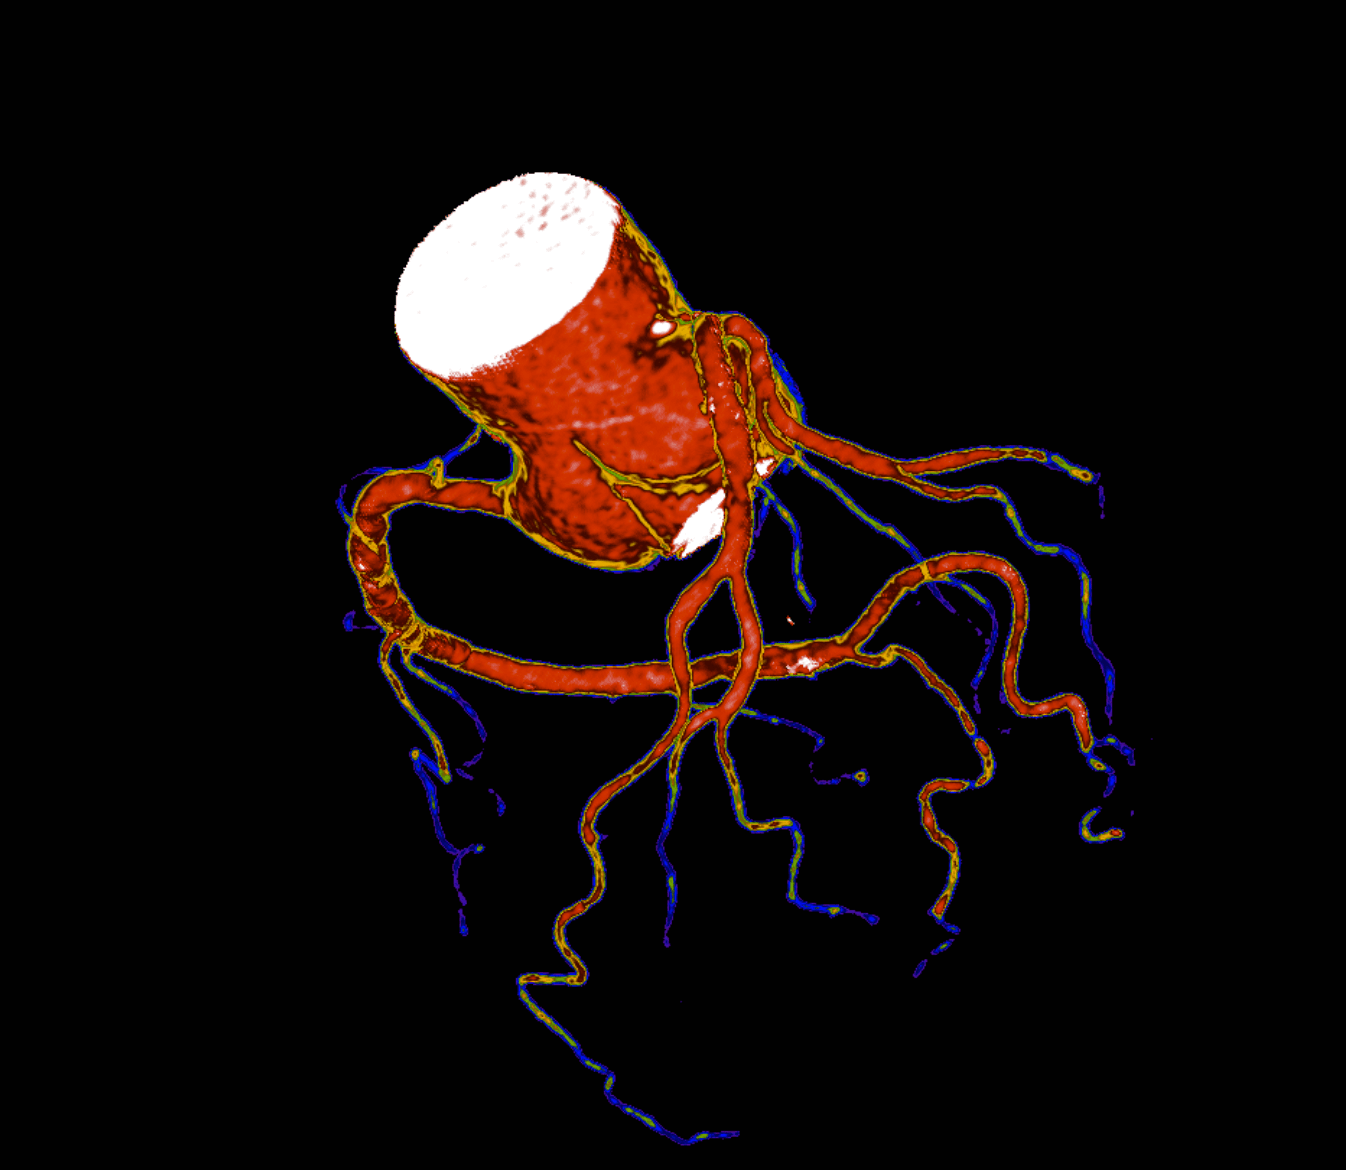

O que vemos nessa imagem???↓↓↓↓↓↓Resposta:O aneurisma do seio de Valsava é uma condição rara, que geralmente só causa sintomas após sua ruptura. É ocasionado pela separação ou pela falta de fusão e…